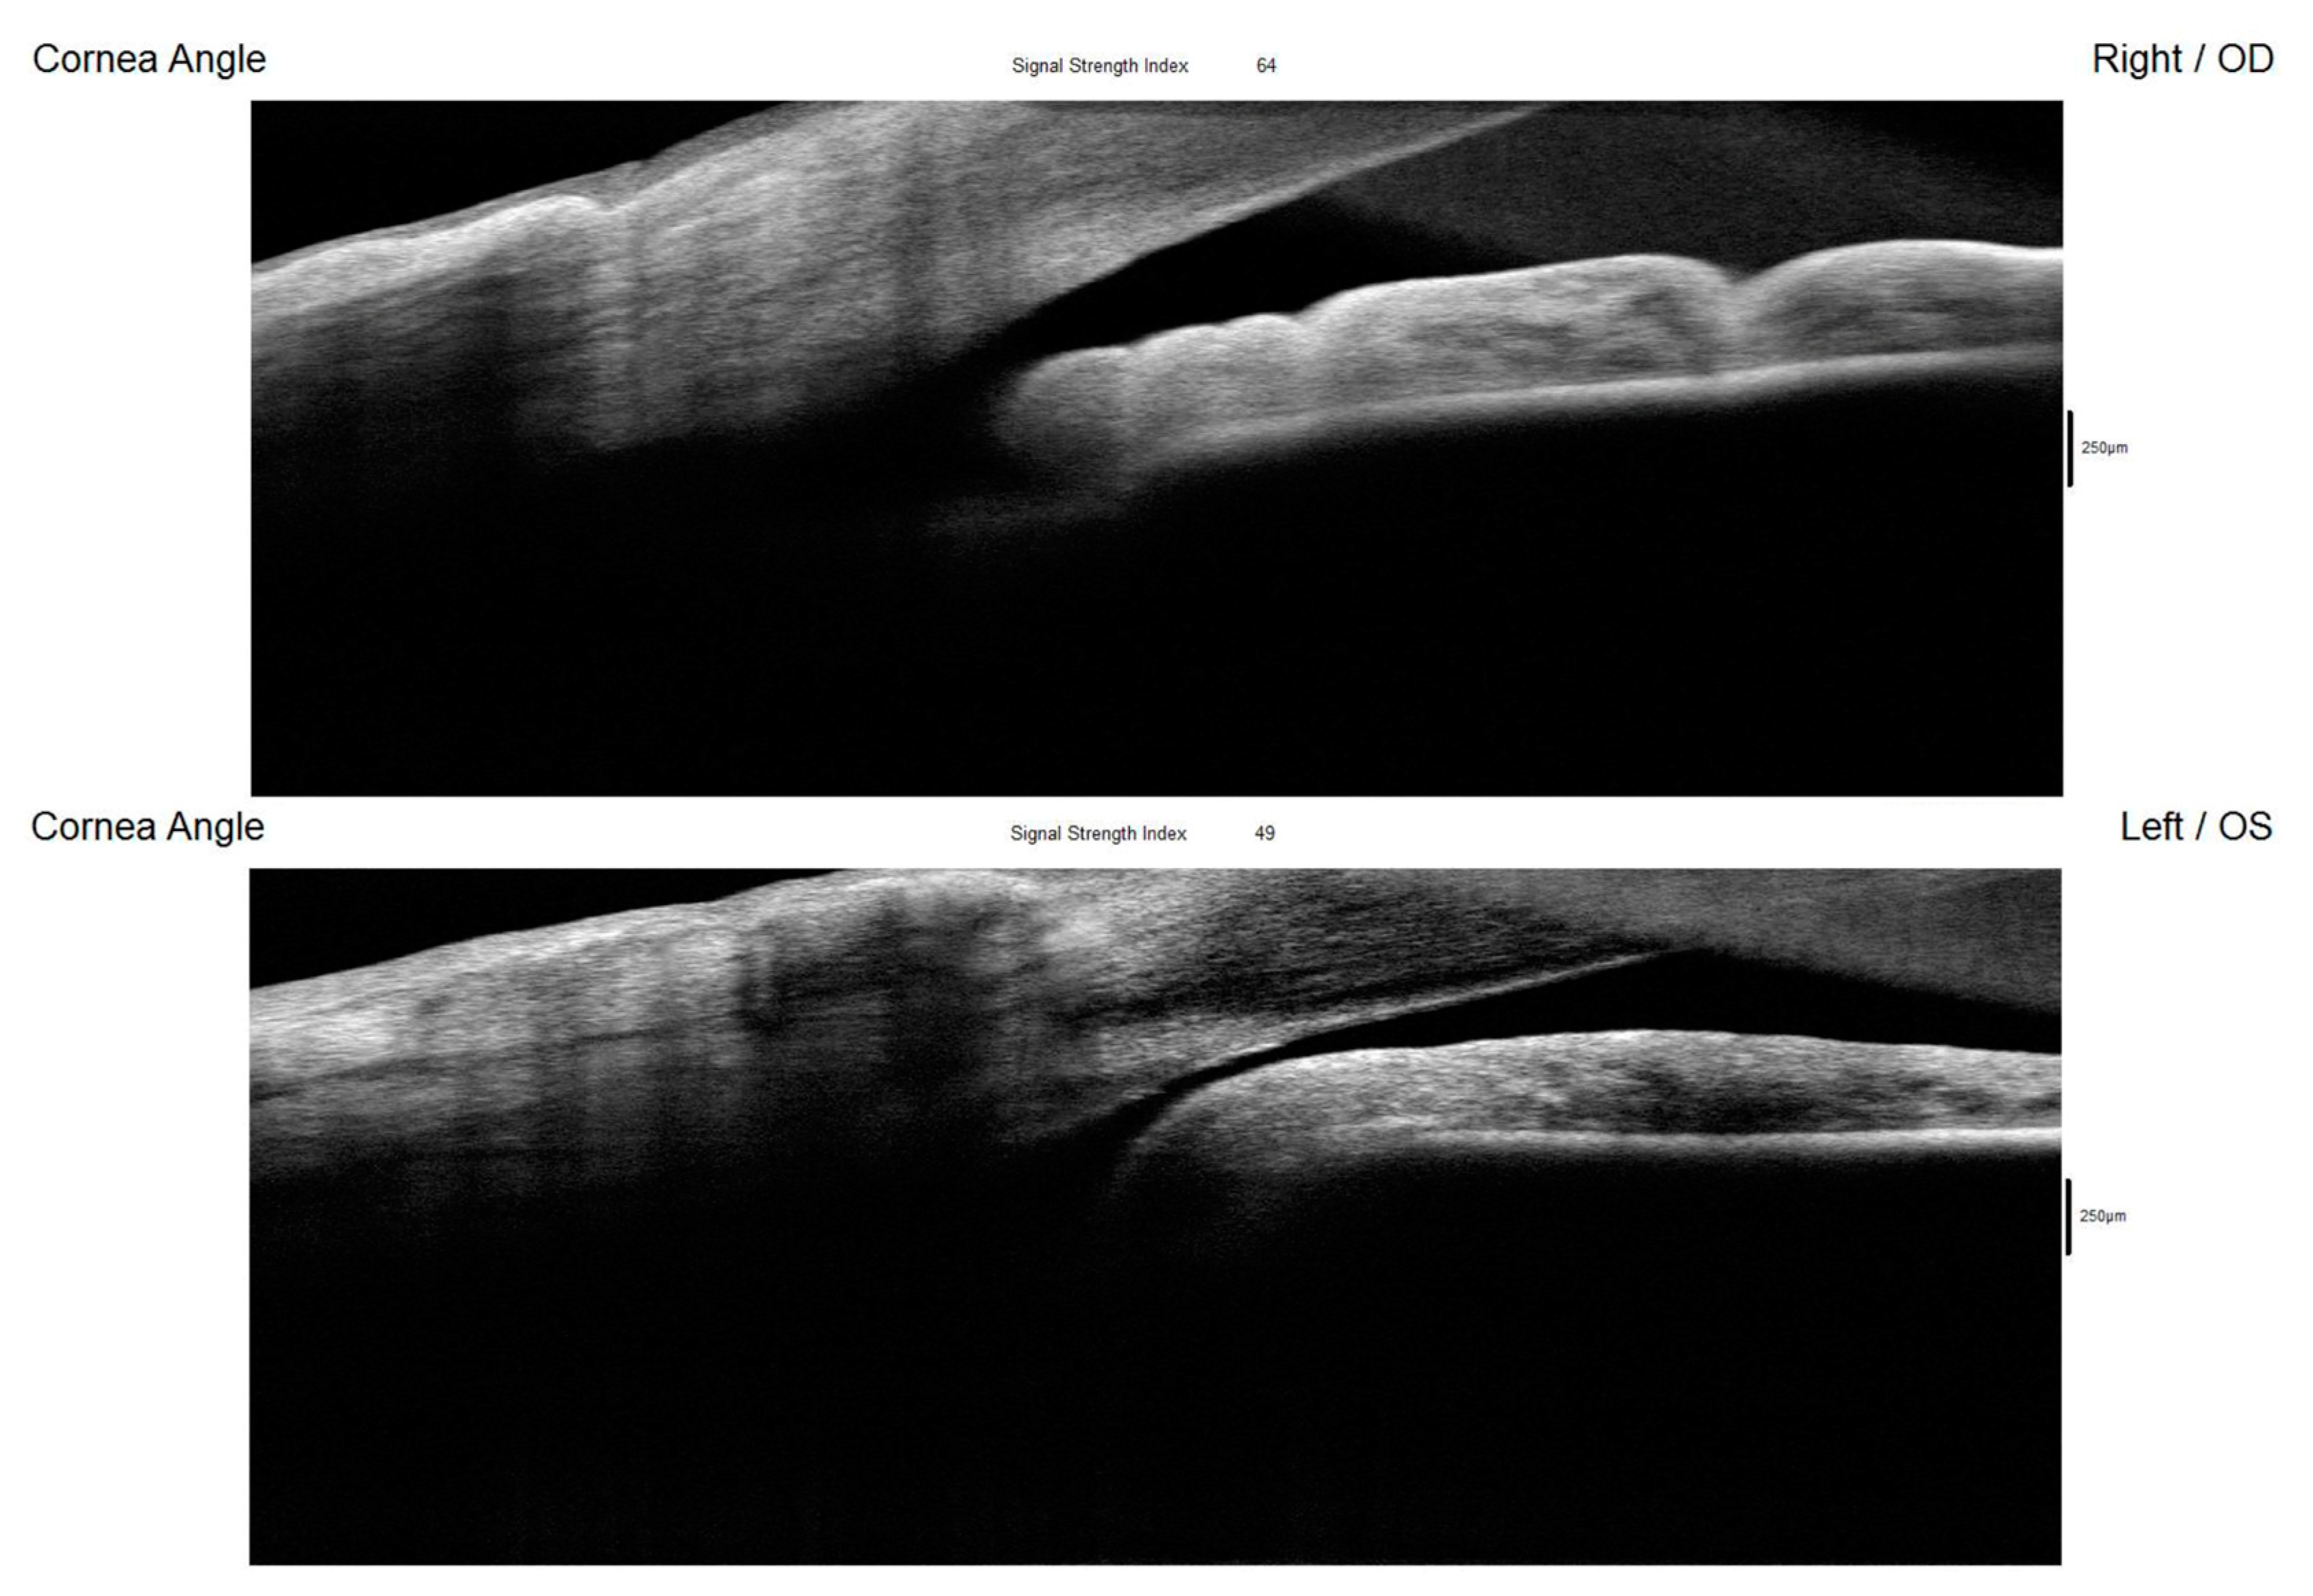

Figure 5. The AS-OCT (RTVue, Optovue Inc., Fremont, CA, USA) offered comprehensive imaging of the anterior segment structures, primarily emphasizing the cornea and corneal angle. While it also visualized the iris, its capability for retroiridian imaging was limited, preventing assessments of this space. The device revealed a narrow and closed angle in the left eye (Figure 5). This finding aligns with the results obtained from gonioscopy and UBM, which similarly indicated a compromised angle configuration. Figure 5 shows AS-OCT of the right and left eyes showing an open corneal angle in the right eye (upper picture) and a closed angle in the left eye (lower picture) resulting from the posterior displacement of the ciliary body cysts. OD: right eye; OS: left eye.

Figure 6. AS-OCT of the left eye showing a postoperative open corneal angle. The yellow arrow points to the presence of ciliary body cysts and the anterior displacement towards the anterior chamber angle. OS: left eye. The diagnosis of unilateral reverse pupillary block associated with ciliary body cysts and PEX was established, based on a combination of clinical findings, gonioscopy, UBM, and AS-OCT, which have emerged as invaluable diagnostic tools in these cases [7,8]. Evaluation of the anterior segment with Scheimpflug tomography (Pentacam; Oculus GmbH, Wetzlar, Germany) together with optical biometry (IOL Master 500, Carl Zeiss Meditec AG, Jena, Germany) was performed before and after surgery of the left eye to achieve a more objective evaluation of the anterior segment structures, including the anterior chamber depth (ACD), anterior chamber angle (ACA), lens thickness (LT), and axial length (AL), for a better understanding of their behaviour in this case. The comparison of eye measurements taken before and after surgery were taken for a better objective analysis. For the right eye (RE) before surgery, the anterior chamber depth (ACD) was 2.70 mm, the anterior chamber angle (ACA) was 29.8, the lens thickness (LT) was 4.78 mm, and the axial length (AL) was 23.04 mm. After the surgery, measurements from the left eye (LE) show an ACD of 2.66 mm, an ACA of 30.9, an LT of 4.76 mm, and an AL of 23.00 mm. The surgery was performed on the left eye (LE). These measurements helped in evaluating changes in the anterior chamber and lens thickness due to surgical intervention. While the right eye showed minimal changes, with slight decreases in the anterior chamber depth and axial length, the results highlight changes in the anterior segment parameters of the left eye, which was the only eye operated on. The anterior chamber depth increased notably from 1.90 mm to 3.23 mm, indicating a deepening likely due to the communication (trabeculectomy) made between the chambers to break the reverse pupillary block. Meanwhile, the anterior chamber angle decreased from 37.0° to 33.0°, suggesting some narrowing while remaining relatively wide. We believe that this may be due to the presence of the ciliary body cysts which are still causing pressure behind the iris in the angle. The lens thickness decreased from 5.11 mm to 4.78 mm, implying repositioning. These findings underscore the surgical impact on the left eye’s dynamics, essential for assessing postoperative outcomes. Posterior segment OCT revealed normal retinal nerve fibre layer and ganglion cell layer thicknesses in the right eye, along with an intact internal limiting membrane-to-retinal pigment epithelium thickness. In contrast, the left eye exhibited a more excavated neuroretinal rim compared with the right eye, and a reduced ganglion cell layer thickness, with an intact macular structure. Considering the clinical features observed in the patient, including significantly elevated IOP and noted impairment of the optic nerve and visual field, the decision was made to proceed with trabeculectomy with mitomycin C (MMC) in the left eye, rather than performing a peripheral iridotomy. In our evaluation during the slit lamp examination or while performing UBM, we did not observe any additional factors or unusual behaviours of the iris (iridodonosis) or the lens (phacodonosis). Additionally, during the surgery procedure (trabeculectomy), careful evaluation and measures were taken to see if there was any intraoperative reaction of the structures or the aqueous humour when the iridectomy was performed. Postoperative observations revealed control of the IOP. At one month and three months after the surgery, the IOP measurements demonstrated a significant improvement: the right eye measured 17 mmHg and 18 mmHg, while the left eye measured 10 mmHg and 11 mmHg, respectively. Importantly, these measurements were recorded without the use of any topical or systemic medications, indicating that the trabeculectomy successfully managed the IOP. Given the normal examination findings in the right eye and the absence of any clinical manifestations or concerns, it was decided to continue with a strategy of observation for the right eye, monitoring it without immediate intervention. This approach allows for ongoing assessment while minimizing unnecessary treatments. Overall, the outcomes of the trabeculectomy for the left eye were favourable, as evidenced by both the controlled IOP and the stability of the patient’s ocular health in the right eye. The way reverse pupillary block developed in our case is interesting. In a normal eye, aqueous humour is produced by the ciliary body and flows from the posterior chamber through the pupil into the anterior chamber, where it eventually drains out through the trabecular meshwork. In certain conditions, such as in the presence of ciliary tumours or iridociliary cysts, like in our case, we initially hypothesized that due to the anterior displacement that the iridociliary cysts make towards the anterior chamber angle, they can close the structure and lower the outflow of the aqueous humour. This can lead to an increase in pressure in the anterior chamber and consequently a misdirection of the aqueous humour to the posterior chamber. This change in aqueous humour dynamics between both chambers can cause the iris to bow backward towards the lens, creating a seal at the pupillary margin, and consequently predisposing it to the development of a pupillary block. As the iris moves backward (bowing), it may further exacerbate the blockage by pressing against the crystalline lens. As the pupillary aperture becomes more restricted due to the backward bowing of the iris and the resulting blockage, it becomes harder for aqueous humour to exit the posterior chamber. This creates a negative pressure effect, pulling the iris even further back. Therefore, the anatomical changes induced by the ciliary body cysts alter the normal dynamics of the iris and lead to increased contact with neighbouring structures, hindering aqueous humour outflow and leading to the development of a reverse pupillary block. Additionally, we believe that the pseudoexfoliative material, which consists of flaky, fibrillar deposits, along with any associated inflammatory components, may exacerbate this condition in a manner similar to the mechanisms observed in PDS [9]. In this syndrome, the shedding of pigment granules from the iris leads to increased IOP due to obstruction of the trabecular meshwork. In our hypothesis, the pseudoexfoliative material may similarly interact with the iris, resulting in inflammatory responses that further compromise the integrity of the anterior chamber angle. This interaction likely renders the iris more flaccid and susceptible to stretching and displacement, particularly in the presence of elevated pressures or abnormal anatomical configurations. As the iris becomes more pliable, it may lose its normal rigidity and structural support, allowing it to bow or shift more easily in response to mechanical forces, such as those exerted by the ciliary body cysts or the accumulation of pseudoexfoliative material. As a result of these changes, the iris might adhere to regions populated with pseudoexfoliative material within the anterior segment of the eye. This adherence can create a seal that prevents aqueous humour from flowing freely from the posterior to the anterior chamber, effectively leading to a reverse pupillary block. This reversed condition not only contributes to an additional elevation of IOP but may also facilitate the progression of glaucomatous changes, as the impaired drainage exacerbates the pressure buildup within the eye. Another potential hypothesis is that this patient may be experiencing both PDS and PEX concurrently, described in the literature as an overlap syndrome [10]. Although there is limited research on the simultaneous occurrence of these two conditions, some reported cases have indicated that individuals can exhibit both pathologies [11]. This phenomenon invites consideration of whether the simultaneous presence of these syndromes occurs by chance or is the result of the manifestation of two separate genetic mutations in the same individual. It is important to note that while PDS and PEX share certain clinical features, they are generally recognized as distinct clinical entities, each with their own genetics. For instance, while PDS is characterized by the shedding of pigment granules from the iris, PEX involves the accumulation of fibrillar material on the lens and other intraocular structures; both contribute to increased IOP and other ocular complications in different ways, as well as the risk of developing glaucoma. To the best of our knowledge, we present a very rare case of bilateral ciliary body cysts, manifesting unilaterally with reverse pupillary block, in conjunction with PEX, subsequently leading to angle-closure glaucoma. The interplay between ciliary body cysts and pseudoexfoliative material, coupled with associated inflammatory responses, plays a critical role in altering iris dynamics. This alteration can set off a cascade of events culminating in reverse pupillary block and its associated complications. The iridotrabecular contact induced by ciliary body cysts leads to an increase in aqueous flow resistance, elevating anterior chamber pressure that induces a backwards displacement of the iris, increasing iris–lens contact and reducing transpupillary aqueous humour flow. The anatomical changes of the iris in PEX could favor the appearance and further persistence of a reverse pupillary block.